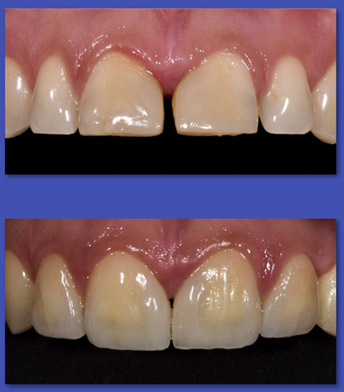

10. REHABILITACIÓN ORAL

La rehabilitación oral es una especialidad dentro de la odontología que combina en forma integral las áreas de prótesis fija, prótesis removible, operatoria, oclusión e Implante dental, que realiza el diagnóstico y plan de tratamiento adecuado al paciente de alta complejidad que requiere recuperar su salud bucal a través de las técnicas más modernas de rehabilitación. A su vez, establece estrecha relación con las demás disciplinas de la odontología, como periodoncia, endodoncia y ortodoncia.

ANTES

DESPUÉS